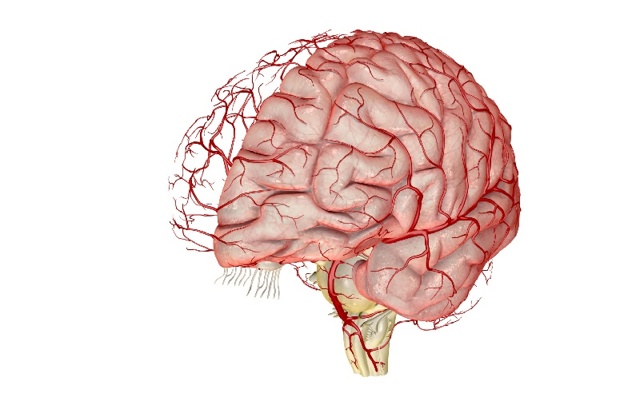

Строение сосудов головного мозга

Человеческий мозг состоит из левого и правого полушария, кровоснабжение которых осуществляется по магистральным сосудам: 1 основной и 2 сонным артериям. Отток крови идёт по яремным парным венам.

Основная (базилярная) артерия мозга сформирована в результате слияния 2 позвоночных артерий и снабжает кровью мозжечок, продолговатый отдел и шею. От неё отходят 2 задние артерии. Соединяясь с ответвлениями сонных артерий и между собой, они образуют виллизиев круг, поставляющий кровь в мозговые ткани. Позвоночные и спинномозговые артерии в продолговатом мозге формируют круг Захарченко.

Между твёрдой мозговой оболочкой пролегают синусы головного мозга. В них поступает кровь их наружных, внутренних вен и попадает в яремные сосуды головы и шеи.